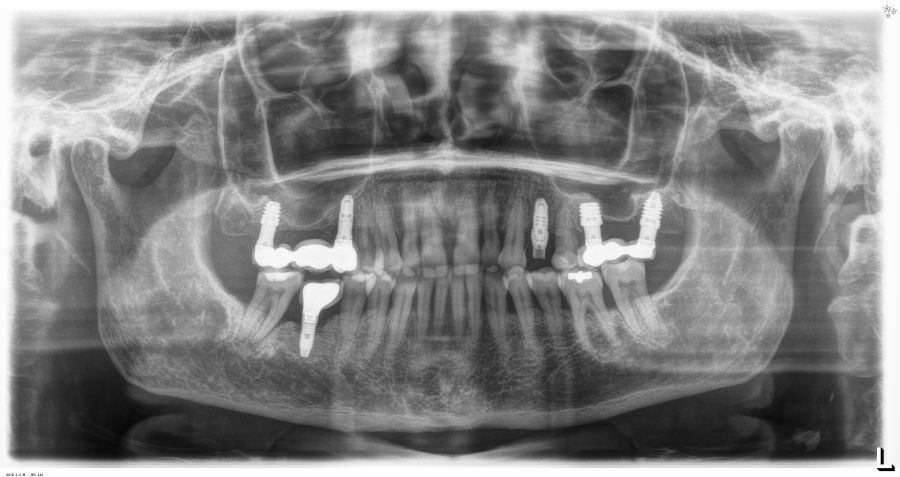

Los pacientes acudieron cada 6 meses a la realización de radiografías panorámicas y periapicales de control y sobre estas radiografías y se realizaron las mediciones necesarias para comprobar la estabilidad y pérdida ósea crestal de los implantes. Una vez obtenida la radiografía en formato digital fue calibrada mediante un software específico (Sidexis measure y Digora) a través de una longitud conocida en la radiografía como es el implante dental. Una vez introducimos la medida de calibración, el programa informático realizó un cálculo basado en esta medida para eliminar la magnificación, pudiendo realizar mediciones lineales exentas de este error. La pérdida ósea marginal se definió como la distancia entre el hombro del implante y el primer punto de contacto óseo visible sobre su superficie. En estas visitas se realiza además sondaje de los implantes y se anotaron los posibles signos y síntomas de periimplantitis o mucositis (sangrado espontáneo, al sondaje, inflamación o supuración).

Fueron reclutados 21 pacientes en los que se colocaron 21 implantes que reunían los criterios de inclusión anteriormente descritos. Todos los implantes fueron de una longitud de 6,5 mm y el diámetro osciló entre los 3,50 mm el más frecuente con un 66,7% del total, hasta 3 mm en el 14,3%, siendo el restante 19% de diámetro de 3,3 mm. En cuanto a la disposición de los implantes, el 61,8% se situaron en la mandíbula siendo la posición más frecuente en localización de 45 y 46 con un 19% para cada localización. El 38,2% restante se situaron en el maxilar superior, siendo la localización más frecuente en las posiciones de 14 y 15 con un 9,5% cada una de ellas. El resto de las localizaciones se muestran en la Figura 1. El tipo óseo de los implantes insertados fue tipo II en el 66,7% de los casos, de tipo III en el 23,8% y de tipo I en el 9,5%. Si lo distribuimos por regiones anatómicas el más frecuente para el maxilar fue el tipo II (60%) y para la mandíbula también (54,5%). La distribución de los tipos óseos en función de la región se muestra en la Figura 2. El torque medio de inserción de los implantes fue de 37,14 Ncm (+/- 14,54). Los torques en función del tipo óseo y la localización anatómica se muestran en las Figuras 3 y 4. En 11 de los pacientes se llevó a cabo una carga inmediata, y en el resto una diferida.

En cuanto a la rehabilitación protésica, en todos los casos se utilizó una prótesis atornillada con transepitelial para prótesis unitaria. La supervivencia de las prótesis fue del 100%, sin encontrarse fracaso en ninguna de ellas al igual que los implantes, con un tiempo de seguimiento de tres años. Durante el primer año, en las visitas de control, ninguno de los implantes mostró sangrado al sondaje ni inflamación de los tejidos periimplantarios. La media de la pérdida ósea en este punto fue de 0,32 mm (+/- 0,60) y la media de la pérdida ósea distal de 0,31 (+/- 0,48). A los dos años, no se registraron tampoco signos inflamatorios en ninguno de los implantes y la pérdida ósea mesial del conjunto fue de media de 0,38 mm (+- 0,54) y la distal de 0,64 mm (+/- 0,70). En la última visita a los 3 años, los tejidos periimplantarios siguieron estables, sin signos de inflamación y la media de la pérdida ósea mesial fue de 0,40 mm (+/- 0,53) y la distal de 0,69 (+/- 0,55) (Figura 5). En las Figuras 6-12 se muestra uno de los casos incluidos en el estudio.